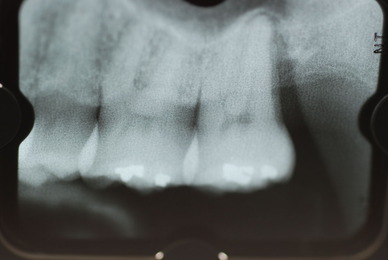

![0a9e48b6-s[1]](https://livedoor.blogimg.jp/netdental/imgs/4/0/40e1507e.jpg)